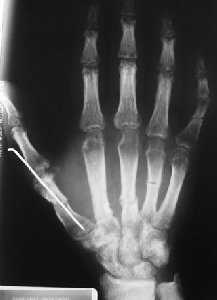

Schiacciamento 2° e 3° dito, mano con fratture multiple

“Mano negativa”